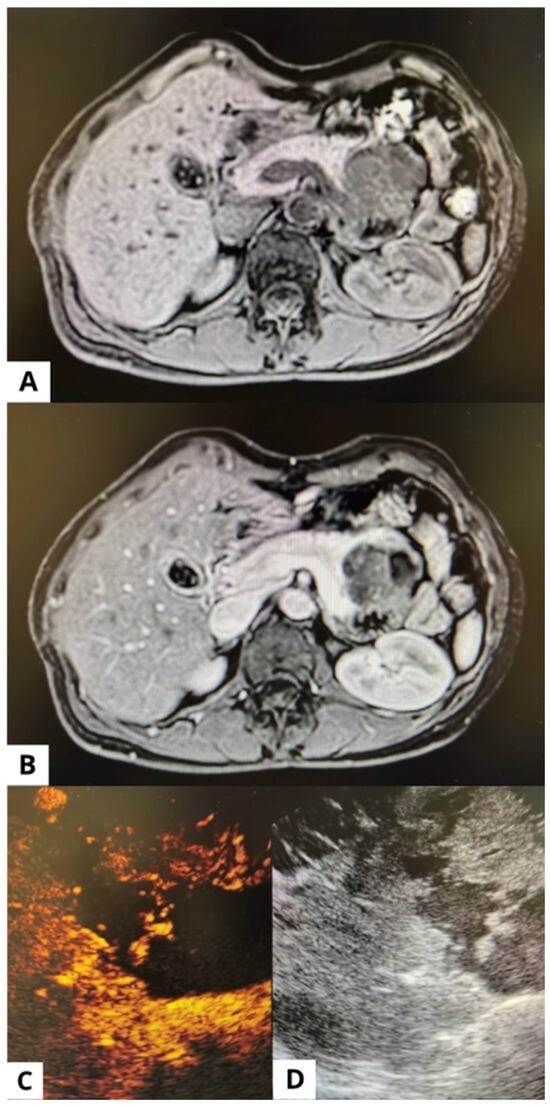

Elastography and Contrast-Guided Sampling Using Endoscopic Ultrasound-Guided Fine-Needle Biopsy for Evaluation of Large Gastric Subepithelial Lesions: A Case Report

Endoscopic ultrasound (EUS) with fine-needle biopsy (FNB) is one of the techniques applied for sampling subepithelial lesions (SELs) of the gastrointestinal tract. Elastography and contrast-enhanced evaluation could permit identification of different patterns among areas of the lesions, depending on their consistence and the [...] Read more.

Endoscopic ultrasound (EUS) with fine-needle biopsy (FNB) is one of the techniques applied for sampling subepithelial lesions (SELs) of the gastrointestinal tract. Elastography and contrast-enhanced evaluation could permit identification of different patterns among areas of the lesions, depending on their consistence and the presence of vital cells or necrosis. Targeting a specific area when performing FNB in the case of large lesions could potentially permit an increase in accuracy and reduce the need for re-sampling. A 61-year-old woman was admitted reporting severe abdominal pain. The patient underwent cholecystectomy many years ago. She had no known family history of gastrointestinal, hepatic, biliary, or pancreatic disease. Laboratory tests were normal. A computed tomography scan showed a large lesion between the stomach and the pancreatic body, suspected to originate from the gastric wall. An endoscopic view showed a large bulging into the gastric lumen and EUS identified a lesion originating from the muscular layer of the gastric wall. Elastography and contrast-enhanced EUS identified two different areas, one softer with lower enhancement (A) and the other harder with higher enhancement after contrast injection (B). FNB was performed targeting both the areas, sending samples for separate histological evaluation. Histology showed a gastrointestinal stromal tumor (GIST), finding differences in amount of necrotic and neoplastic cells between the two areas. EUS-FNB guided by elastography and/or contrast-enhanced EUS could identify differences within large SELs, allowing targeting of areas more likely to collect diagnostic samples. Full article